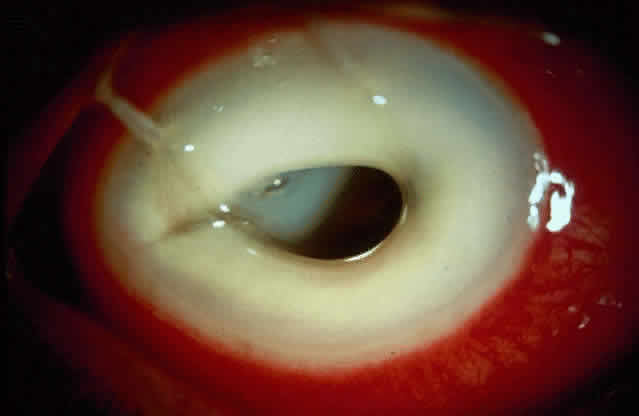

The prevalence of aphakic and pseudophakic corneal edema is high and now constitutes the second most common indication for penetrating keratoplasty (Fig. 6).2 Poor surgical technique, use of noxious pharmalogic agents, poor quality of intraocular lenses, and delay in the diagnosis and treatment of complications aggravates the problem.

Fig. 6. Corneal edema in an eye that underwent intraocular lens implantation with an iris-claw lens.